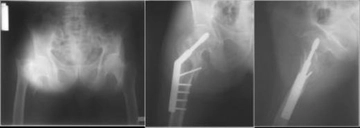

4. Tanı ve Tedavi YöntemleriPelvis bölgesi ağrısının tanısı, hastanın öyküsü, fiziksel muayene ve gerekirse görüntüleme yöntemleri (ultrason, MR vb.) ile konulmaktadır. Tedavi yöntemleri ise ağrının nedenine bağlı olarak değişkenlik göstermektedir. Genel tedavi seçenekleri şunlardır: